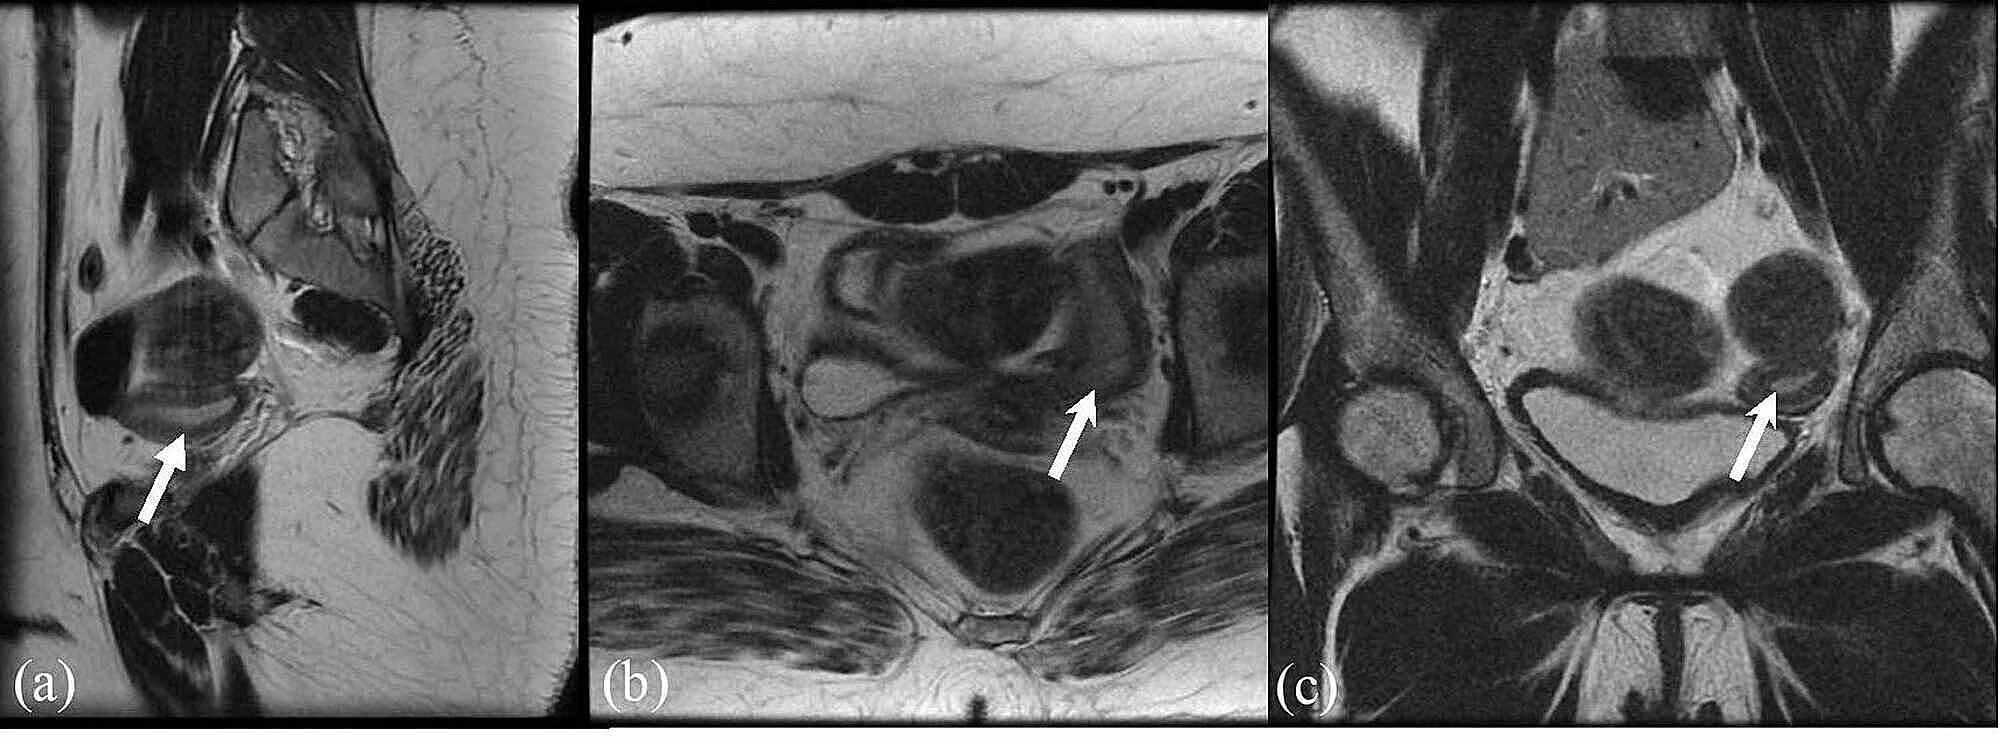

From www.semanticscholar.org

Figure 3 from Ovarian Failure with Absent Uterus in A Rare Mosaic Turner Syndrome Uterus And Ovaries Most women with turner syndrome have streak gonads or immature ovaries and manifest hypergonadotropic hypogonadism. Turner’s syndrome (ts) is depicted as a total or partial absence of one x chromosome that results in ovarian dysgenesis. Turner syndrome is one of the more common chromosome anomalies in humans and represents an important cause of short stature. Turner syndrome happens when a. Turner Syndrome Uterus And Ovaries.

From www.researchgate.net

(PDF) Case Report From epilepsy and uterus didelphys to Turner Turner Syndrome Uterus And Ovaries Turner syndrome is one of the more common chromosome anomalies in humans and represents an important cause of short stature. Turner syndrome (ts) is defined as deficiency of all or part of the second sex chromosome in phenotypic females and is relatively common,. Turner syndrome, also referred to as congenital ovarian hypoplasia syndrome is the most common sex. Turner’s syndrome. Turner Syndrome Uterus And Ovaries.